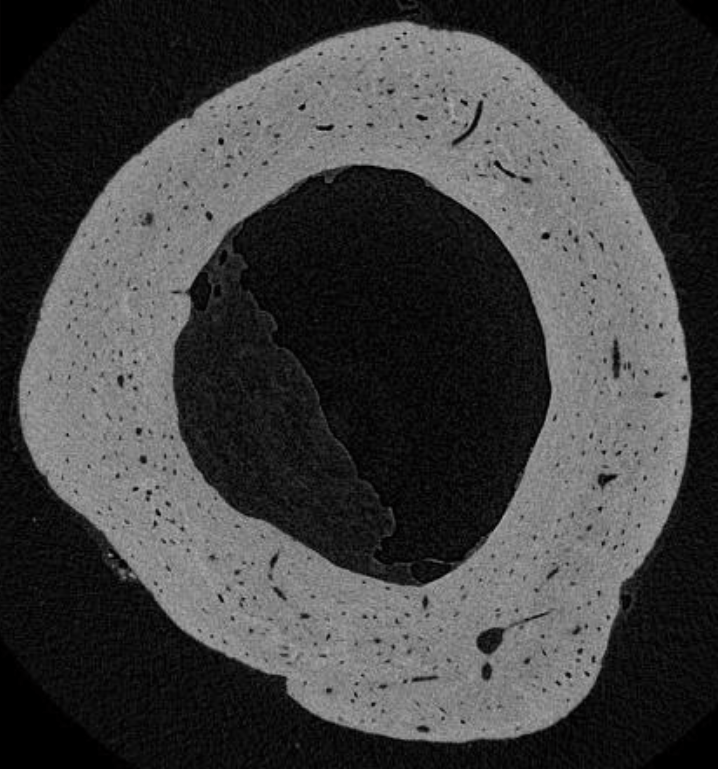

- Advanced yet easy quantitative analysis of cortical and trabecular bone in accordance with ASBMR parameter outputs (BV, TV, Tb.th, ..), including bone mineral density (BMD), tissue mineral density (TMD), and outputs in Hounsfield Units (HU)

Sophisticated imaging process tools within the SkyScan 3D software suite allow for reorientation of the dataset, precise and consistent volume-of-interest from the fracture, and quantitative assessment of new bone formation through the use of robust segmentation protocols.

Never before has the advancement in bone research had such extraordinary resolution, opening up the possibility for submicron imaging and analysis of osteocyte lacunar and blood vessel canal porosity; osteocyte lacunar morphology, osteocyte lacunar separation; vascular network, orientation and anisotropy; as well as determining biomechanical responses.